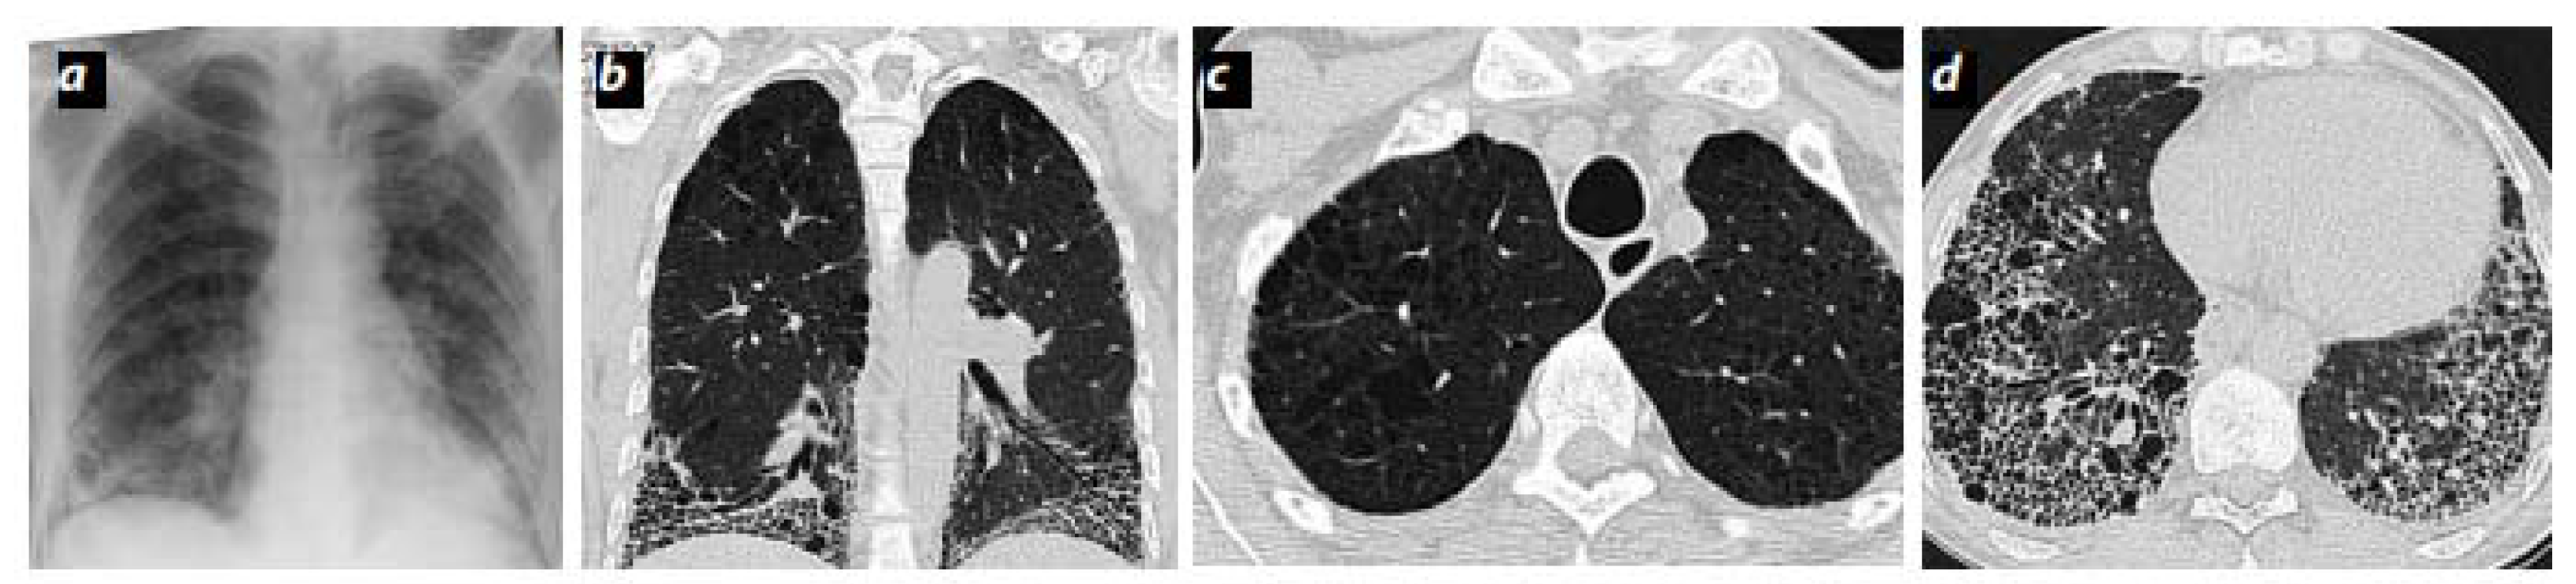

2. Pulmonary Emphysema